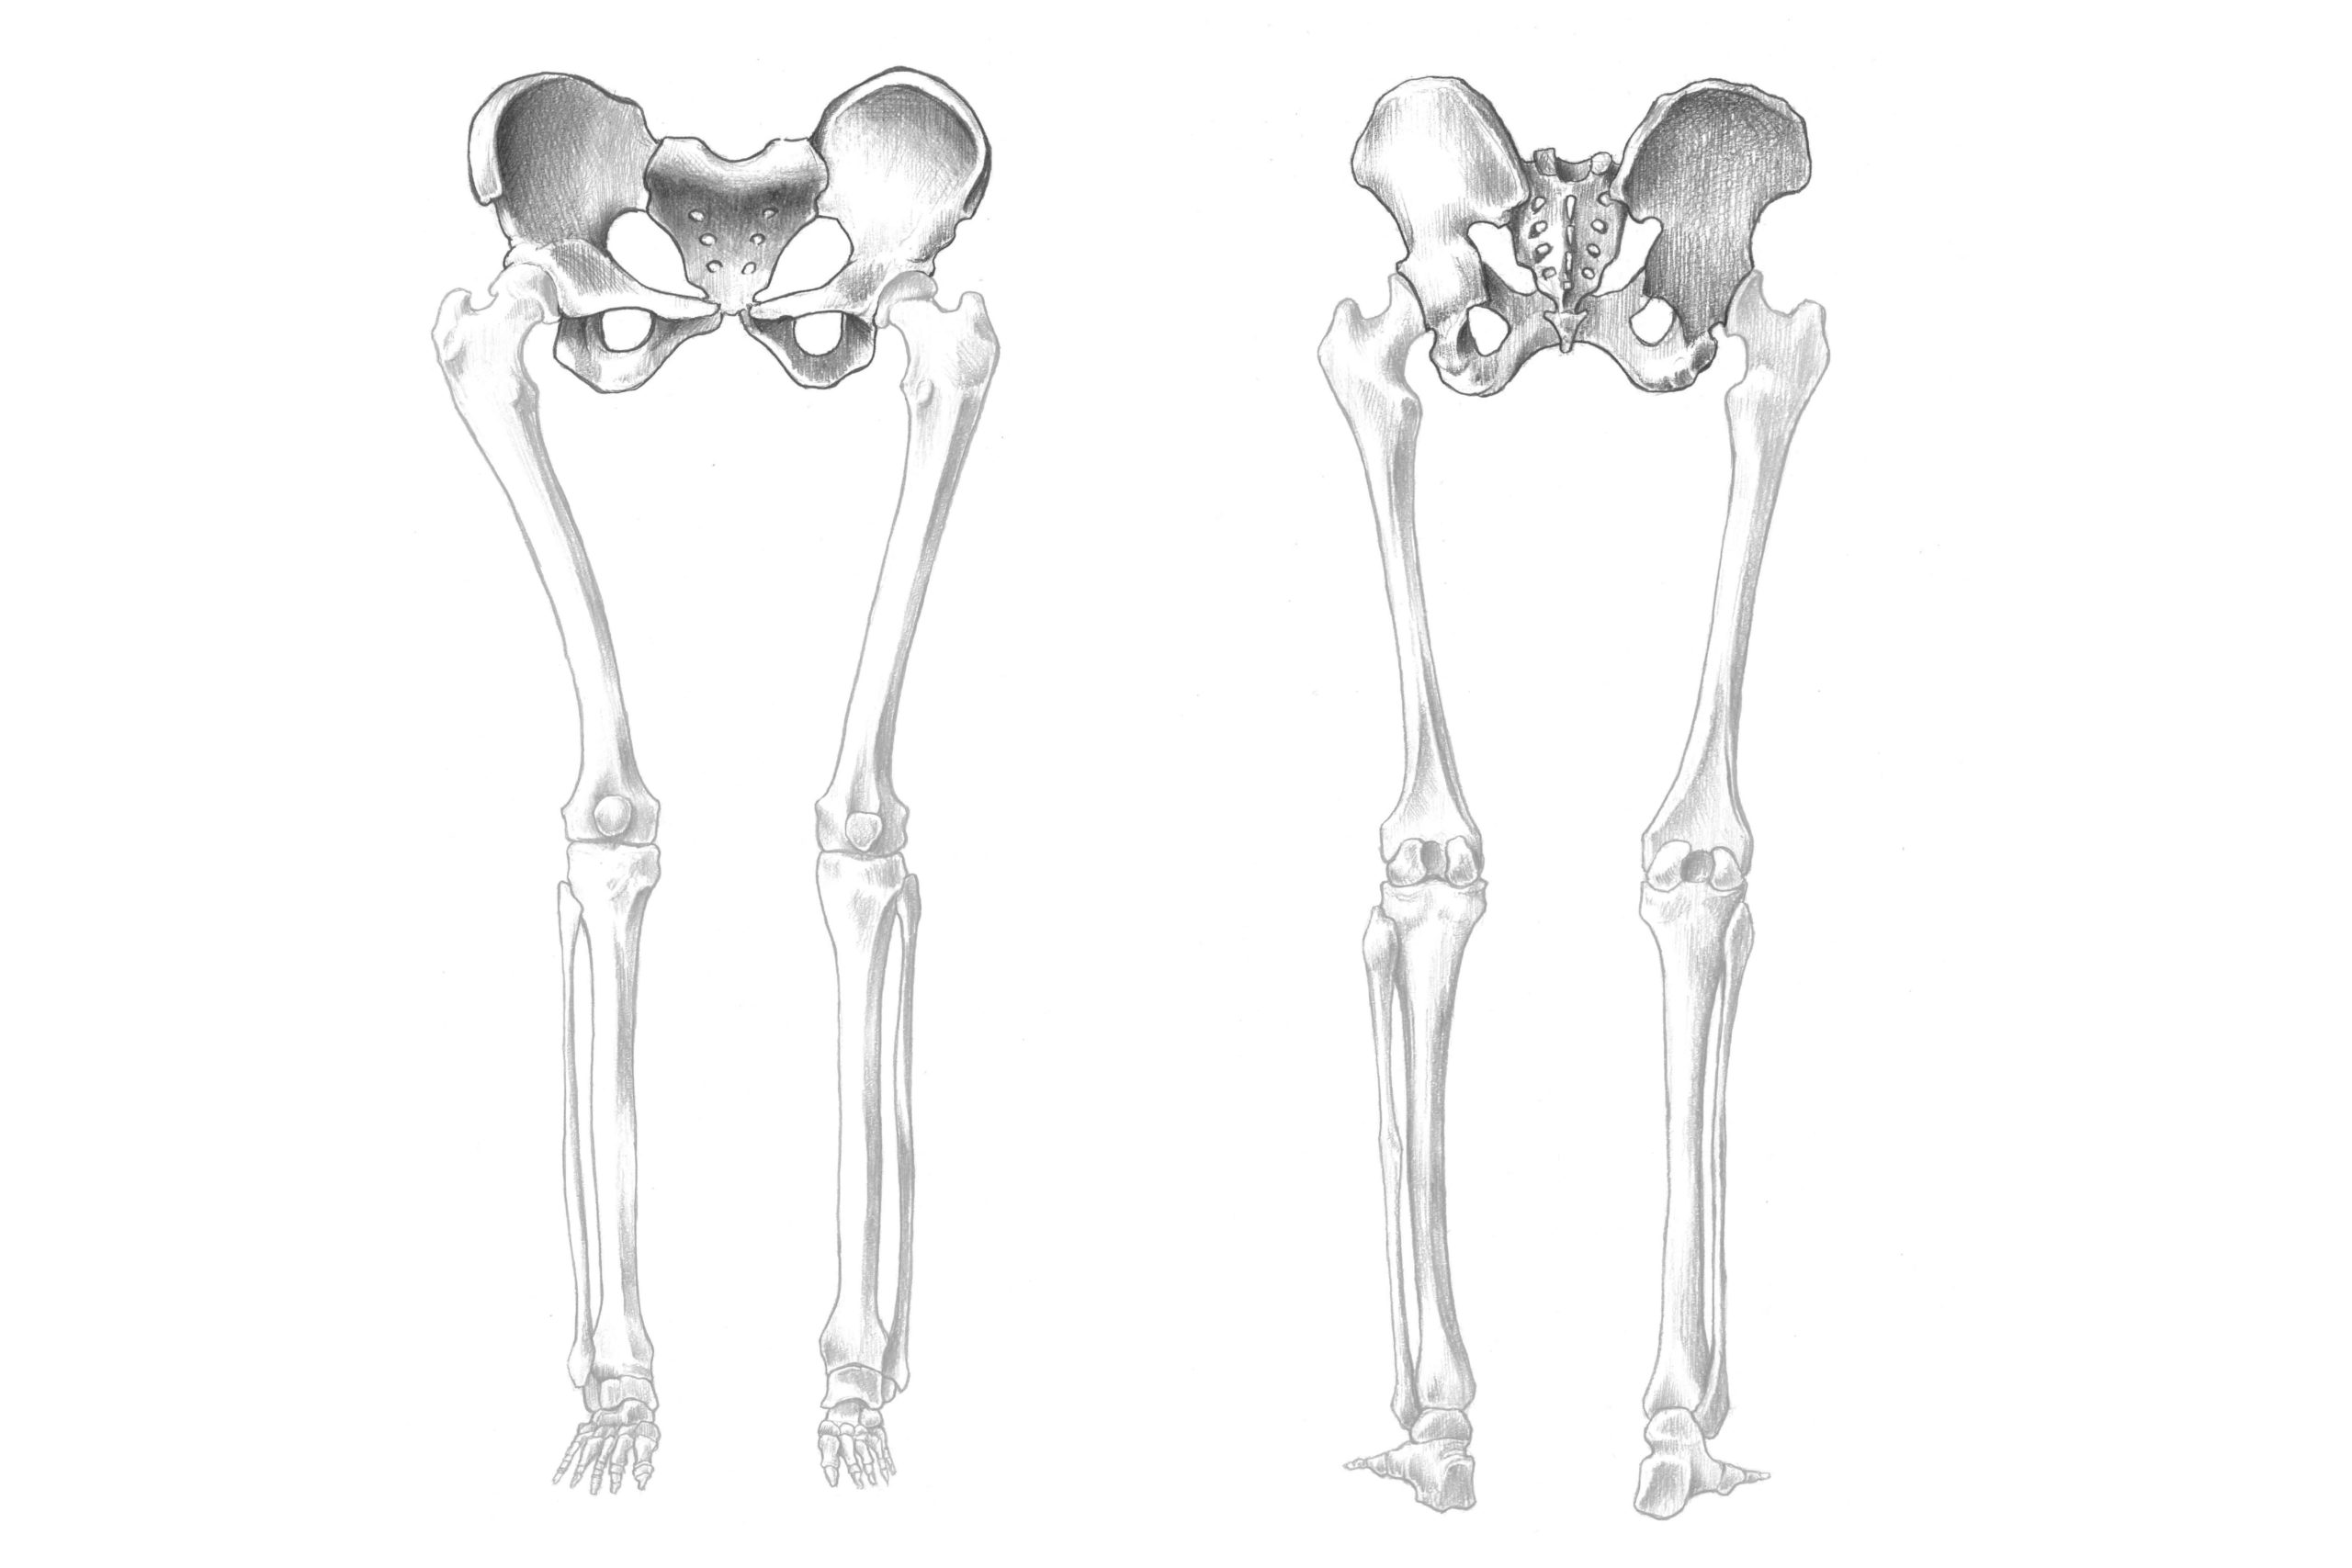

解剖学 12骨盤ってどんな骨 実際のスケッチと一緒に解説 ナツヲカケル 兼業クリエイター雑記

骨格 人体図 下半身 大腿骨 Medicalrf Com の画像素材 イラスト Cgの写真素材ならイメージナビ

解剖学 下半身の骨格をまとめて解説 スケッチ ナツヲカケル 兼業クリエイター雑記

下半身の骨 イラストキット

解剖学 下半身の骨格をまとめて解説 スケッチ ナツヲカケル 兼業クリエイター雑記

解剖学 下肢の骨の構造について知っておこう ナツヲカケル 兼業クリエイター雑記

解剖学 下半身の骨格をまとめて解説 スケッチ ナツヲカケル 兼業クリエイター雑記

下半身の骨 イラストキット

解剖学 下半身の骨格をまとめて解説 スケッチ ナツヲカケル 兼業クリエイター雑記

解剖学 下半身の骨格をまとめて解説 スケッチ ナツヲカケル 兼業クリエイター雑記

解剖学 下半身の骨格をまとめて解説 スケッチ ナツヲカケル 兼業クリエイター雑記

解剖学 下半身の骨格をまとめて解説 スケッチ ナツヲカケル 兼業クリエイター雑記

解剖学 下半身の骨格をまとめて解説 スケッチ ナツヲカケル 兼業クリエイター雑記

解剖学 下半身の骨格をまとめて解説 スケッチ ナツヲカケル 兼業クリエイター雑記

解剖学 下半身の骨格をまとめて解説 スケッチ ナツヲカケル 兼業クリエイター雑記